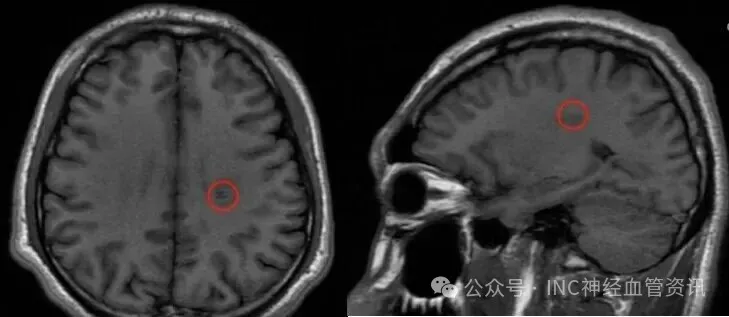

紧急去医院,而MRI检查结果如晴天霹雳:左侧半卵圆中心区有个8.0x11.0mm的类圆形异常信号灶,考虑海绵状血管瘤出血。

2022年5月MRI影像,血管畸形处于急性出血期

半卵圆中心是什么部位?半卵圆中心位于大脑半球深部白质区,其边界上达大脑皮层下缘,下至胼胝体辐射纤维交汇处。负责连接各脑区传递信号,因此在此处手术切除病灶的风险极大,一旦受损可能影响运动功能。